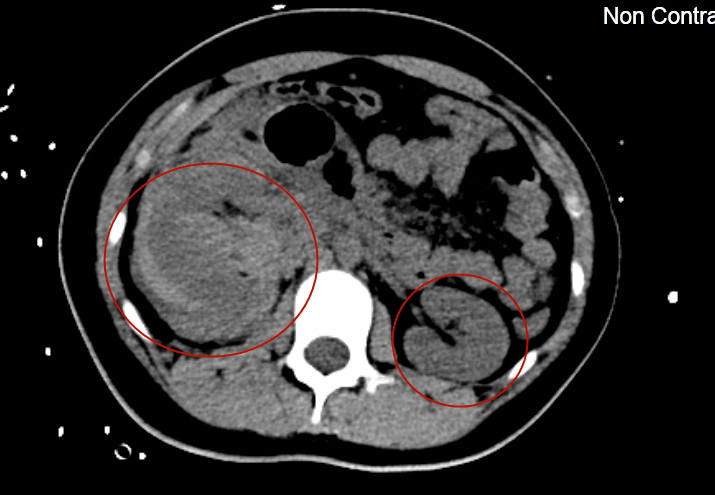

"右侧肾脏有一个直径约10cm的血肿,可能是肿瘤而且已经局部破裂,导致

巨大左肾错构瘤自发性破裂出血1例 - 好大夫在线